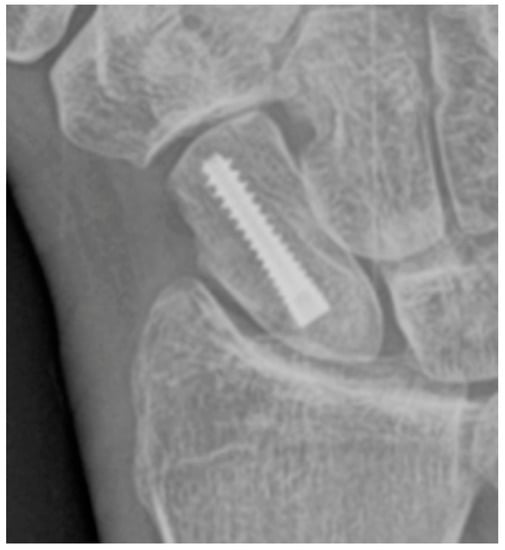

Conservative management of scaphoid fractures consists of cast immobilization across the wrist, including the first metacarpophalangeal joint. This is the most widely used management strategy for scaphoid fractures, particularly when the fracture is stable [2,5,19]. Low rates of morbidity and long-term disability are advantages of a conservative approach; however, this may require a prolonged time to resume work and daily activities of living compared to surgical fixation. The surgical approach involves minimally invasive screw fixation using a compression (e.g., Herbert or Accutrak) screw to allow early mobilization, improving return to activity time over casting. The surgical approach utilizes threaded headless screws (Figure 8), allowing them to be countersunk beneath the articular surface and eliminating the need for removal after fracture healing [17]. Variable threading of the fixation screw promotes compression at the fracture site, facilitating healing. Surgical staple fixation of scaphoid waist fractures is another alternative [20]. Percutaneous screw fixation is contradicted in displaced scaphoid fractures or with nonunion because the fracture may become displaced during the procedure, requiring a subsequent open reduction. A supplementary option for scaphoid fractures with nonunion or sclerosis and/or cystic change is a vascularized bone graft. In these cases, a bleeding surface is re-established at the fracture site for the bone graft containing a vascular pedicle to be incorporated into. The vascular pedicle is typically salvaged from the distal radius (Figure 9a) and inserted into the revitalized fracture gap to re-establish blood flow to the proximal pole (Figure 9b). The vascular pedicle is anastomosed with the radial artery [21].

Figure 8. PA radiograph showing surgical fixation of a scaphoid fracture utilizing a variably threaded headless compression screw, allowing it to be countersunk beneath the articular surface, removing the need for retrieval after the fracture has healed. In this case, the screw has been introduced via a dorsal approach, advanced from proximal to distal.